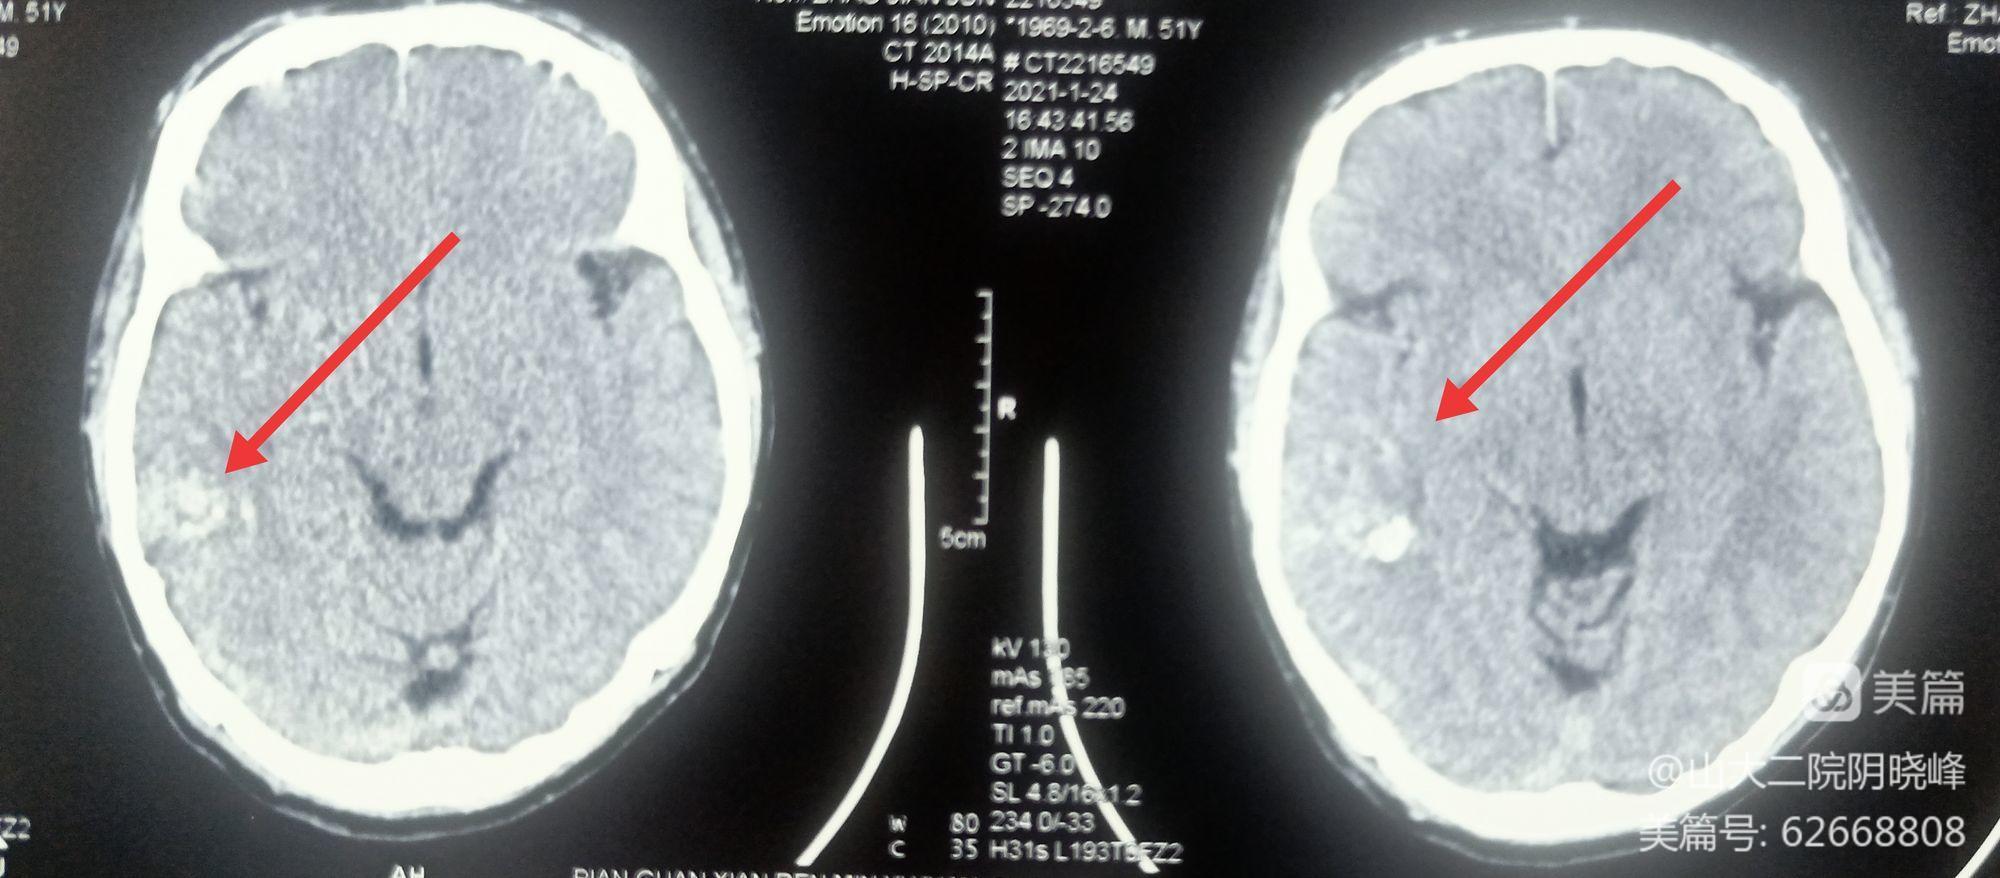

术前头颅CT:右侧颞枕高密度影